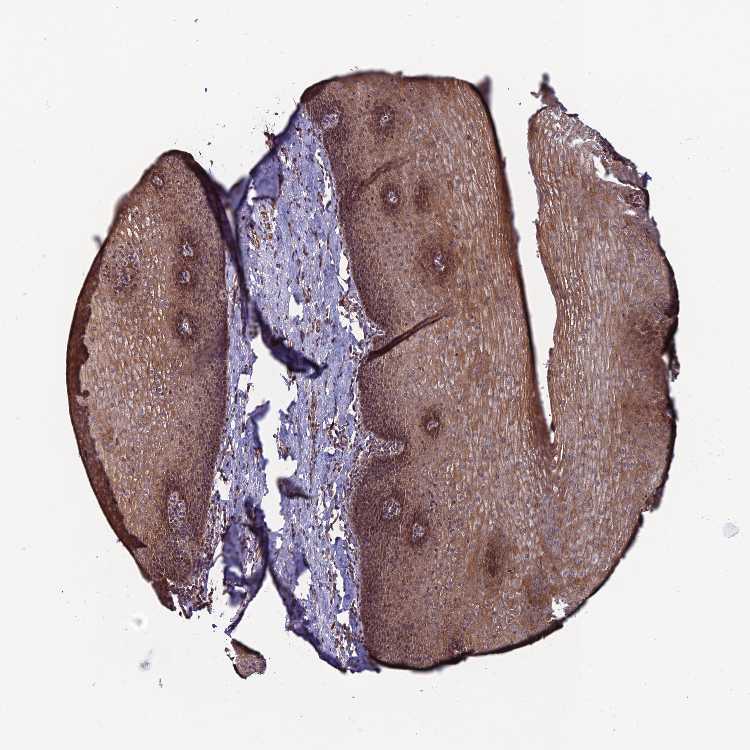

ESOPHAGUS - Antibody stainingi

Antibody staining in the annotated cell types in the current human tissue is reported as not detected, low, medium, or high, based on conventional immunohistochemistry profiling in selected tissues. This score is based on the combination of the staining intensity and fraction of stained cells.

Each image is clickable and will lead to virtual microscopy that enables deeper exploration of all samples and also displays staining intensity scores, fraction scores and subcellular localization as well as patient and tissue information for each sample.

Antibody HPA043812

Squamous epithelial cells Medium